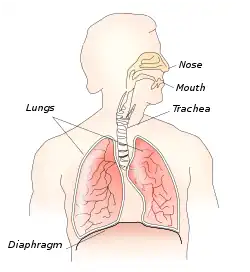

The thoracic diaphragm, or simply the diaphragm (/ˈdaɪəfræm/;[2] Ancient Greek: διάφραγμα, romanized: diáphragma, lit. 'partition'), is a sheet of internal skeletal muscle[3] in humans and other mammals that extends across the bottom of the thoracic cavity. The diaphragm is the most important muscle of respiration,[4] and separates the thoracic cavity, containing the heart and lungs, from the abdominal cavity: as the diaphragm contracts, the volume of the thoracic cavity increases, creating a negative pressure there, which draws air into the lungs.[5] Its high oxygen consumption is noted by the many mitochondria and capillaries present; more than in any other skeletal muscle.[4]

The diaphragm is an upward curved, c-shaped structure of muscle and fibrous tissue that separates the thoracic cavity from the abdomen. The superior surface of the dome forms the floor of the thoracic cavity, and the inferior surface the roof of the abdominal cavity.[7]

The diaphragm is the main muscle of respiration and functions in breathing. During inhalation, the diaphragm contracts and moves in the inferior direction, enlarging the volume of the thoracic cavity and reducing intra-thoracic pressure (the external intercostal muscles also participate in this enlargement), forcing the lungs to expand. In other words, the diaphragm's movement downwards creates a partial vacuum in the thoracic cavity, which forces the lungs to expand to fill the void, drawing air in the process.